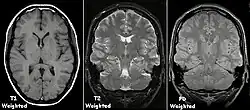

Mit der MRT können Schnittbilder des menschlichen (oder tierischen) Körpers erzeugt werden, die eine Beurteilung der Organe und vieler krankhafter Organveränderungen erlauben. Sie basiert auf sehr starken Magnetfeldern sowie magnetischen Wechselfeldern im Radiofrequenzbereich, mit denen bestimmte Atomkerne (meist die Wasserstoffkerne/Protonen) im Körper resonant angeregt werden, wodurch in einem Empfängerstromkreis ein elektrisches Signal induziert wird. Da somit das zu beobachtende Objekt „selbst leuchtet“ (im Radiofrequenzbereich), unterliegt die MRT nicht dem physikalischen Gesetz zum Auflösungsvermögen optischer Instrumente, nach dem die Wellenlänge der verwendeten Strahlung umso kleiner sein muss, je höher die geforderte Auflösung ist. In der MRT können mit Wellenlängen im Meterbereich (energiearme Radiowellen) Objektpunkte im Submillimeterbereich aufgelöst werden. Die Helligkeit unterschiedlicher Gewebetypen im Bild wird durch deren Relaxationszeiten und den Gehalt von Wasserstoff-Atomen (Protonendichte) bestimmt.[1] Welcher dieser Parameter den Bildkontrast dominiert, wird durch die Wahl des Aufnahmeverfahrens (Pulssequenz) und der Messparameter beeinflusst.

Um eine -gewichtete Aufnahme zu erhalten, setzt man den Rephasierungsimpuls relativ spät, so dass die Spin-Spin-Relaxation Zeit hat, sich auszuwirken; man spricht von einer langen Echozeit TE (). Auch der zeitliche Abstand bis zur nächsten Messung ist sehr lang, damit die (maximale) longitudinale Ausgangsmagnetisierung durch die Spin-Gitter-Relaxation in allen Geweben weitestgehend wieder erreicht wird. Man spricht von einer langen Repetitionszeit TR (). Mit langer TE und langer TR bekommt man helles Signal nur von Geweben mit langer -Zeit. Für eine -Wichtung braucht man umgekehrt kurze TE () und kurze TR (), dann überwiegen die unterschiedlichen Spin-Gitter-Relaxationen verschiedener Gewebe im Bildkontrast. Eine Sequenz mit kurzer TE () und langer TR () erzeugt einen Kontrast, der sich überwiegend nach der Konzentration der Protonen im Gewebe richtet, die praktisch der Anzahl der Wasserstoffatome entspricht; dies ist die sogenannte Protonendichte-(PD-)-Wichtung. Es gibt zahlreiche Weiterentwicklungen dieser einfachen Spinecho-Sequenzen, etwa zur Beschleunigung oder mit Unterdrückung des Fettgewebesignals. Eine klinische MRT-Untersuchung umfasst unterschiedlich gewichtete Bildserien und mehrere räumlichen Ebenen.

Bildbeurteilung

Die Signalstärke der Voxel wird in Grauwerten kodiert abgebildet. Da sie von zahlreichen Parametern abhängt (etwa der Magnetfeldstärke), gibt es keine Normwerte für das Signal bestimmter Gewebe und keine definierte Einheit, vergleichbar den Hounsfield-Units bei der Computertomographie. Die MR-Konsole zeigt nur arbiträre (willkürliche) Einheiten an, die diagnostisch nicht unmittelbar verwertbar sind. Die Bildinterpretation stützt sich stattdessen auf den Gesamtkontrast, die jeweilige Gewichtung (synonym Wichtung) der Messsequenz und die Signalunterschiede zwischen bekannten und unbekannten Geweben. Im Befund wird deshalb bei der Beschreibung einer Läsion nicht von „hell“ oder „dunkel“ gesprochen, sondern von hyperintens für signalreicher, heller, von hypointens für signalärmer, dunkler und von isointens für signalgleich. Bei Röntgenbildern, insbesondere bei der speziellen Röntgentechnik der Computertomographie (CT), werden im Gegensatz dazu die Begriffe hyperdens und hypodens zur Beschreibung des relativen Schwärzungsgrads benutzt.

Je nach Gewichtung kommen die verschiedenen Gewebe in charakteristischer Intensitätsverteilung zur Darstellung:

- In der T1-Wichtung (T1w) erscheint Fettgewebe hyperintens (signalreich, hell) und damit auch fetthaltige/-reiche Gewebe (z. B. Knochenmark). Diese Gewichtung eignet sich daher gut zur anatomischen Darstellung von Organstrukturen und insbesondere nach Kontrastmittelgabe (Gadolinium) zur besseren Abgrenzbarkeit unbekannter Strukturen (z. B. Tumor).

- In der T2-Wichtung (T2w) erscheinen stationäre Flüssigkeiten hyperintens, so dass flüssigkeitsgefüllte Strukturen (z. B. Liquorräume) signalreich und damit hell erscheinen. Dadurch eignet sich diese Gewichtung zur Darstellung von Ergussbildungen und Ödemen sowie z. B. zur Abgrenzung von Zysten gegenüber soliden Tumoren.

- Protonendichte-gewichtete (PDw) Bilder sind flau (weniger Gewebekontrast), aber scharf. Knorpel kann sehr detailliert beurteilt werden. In Verbindung mit einem Fettsättigungsimpuls gehören PDw-Bilder deshalb zum Standard in Gelenkuntersuchungen.